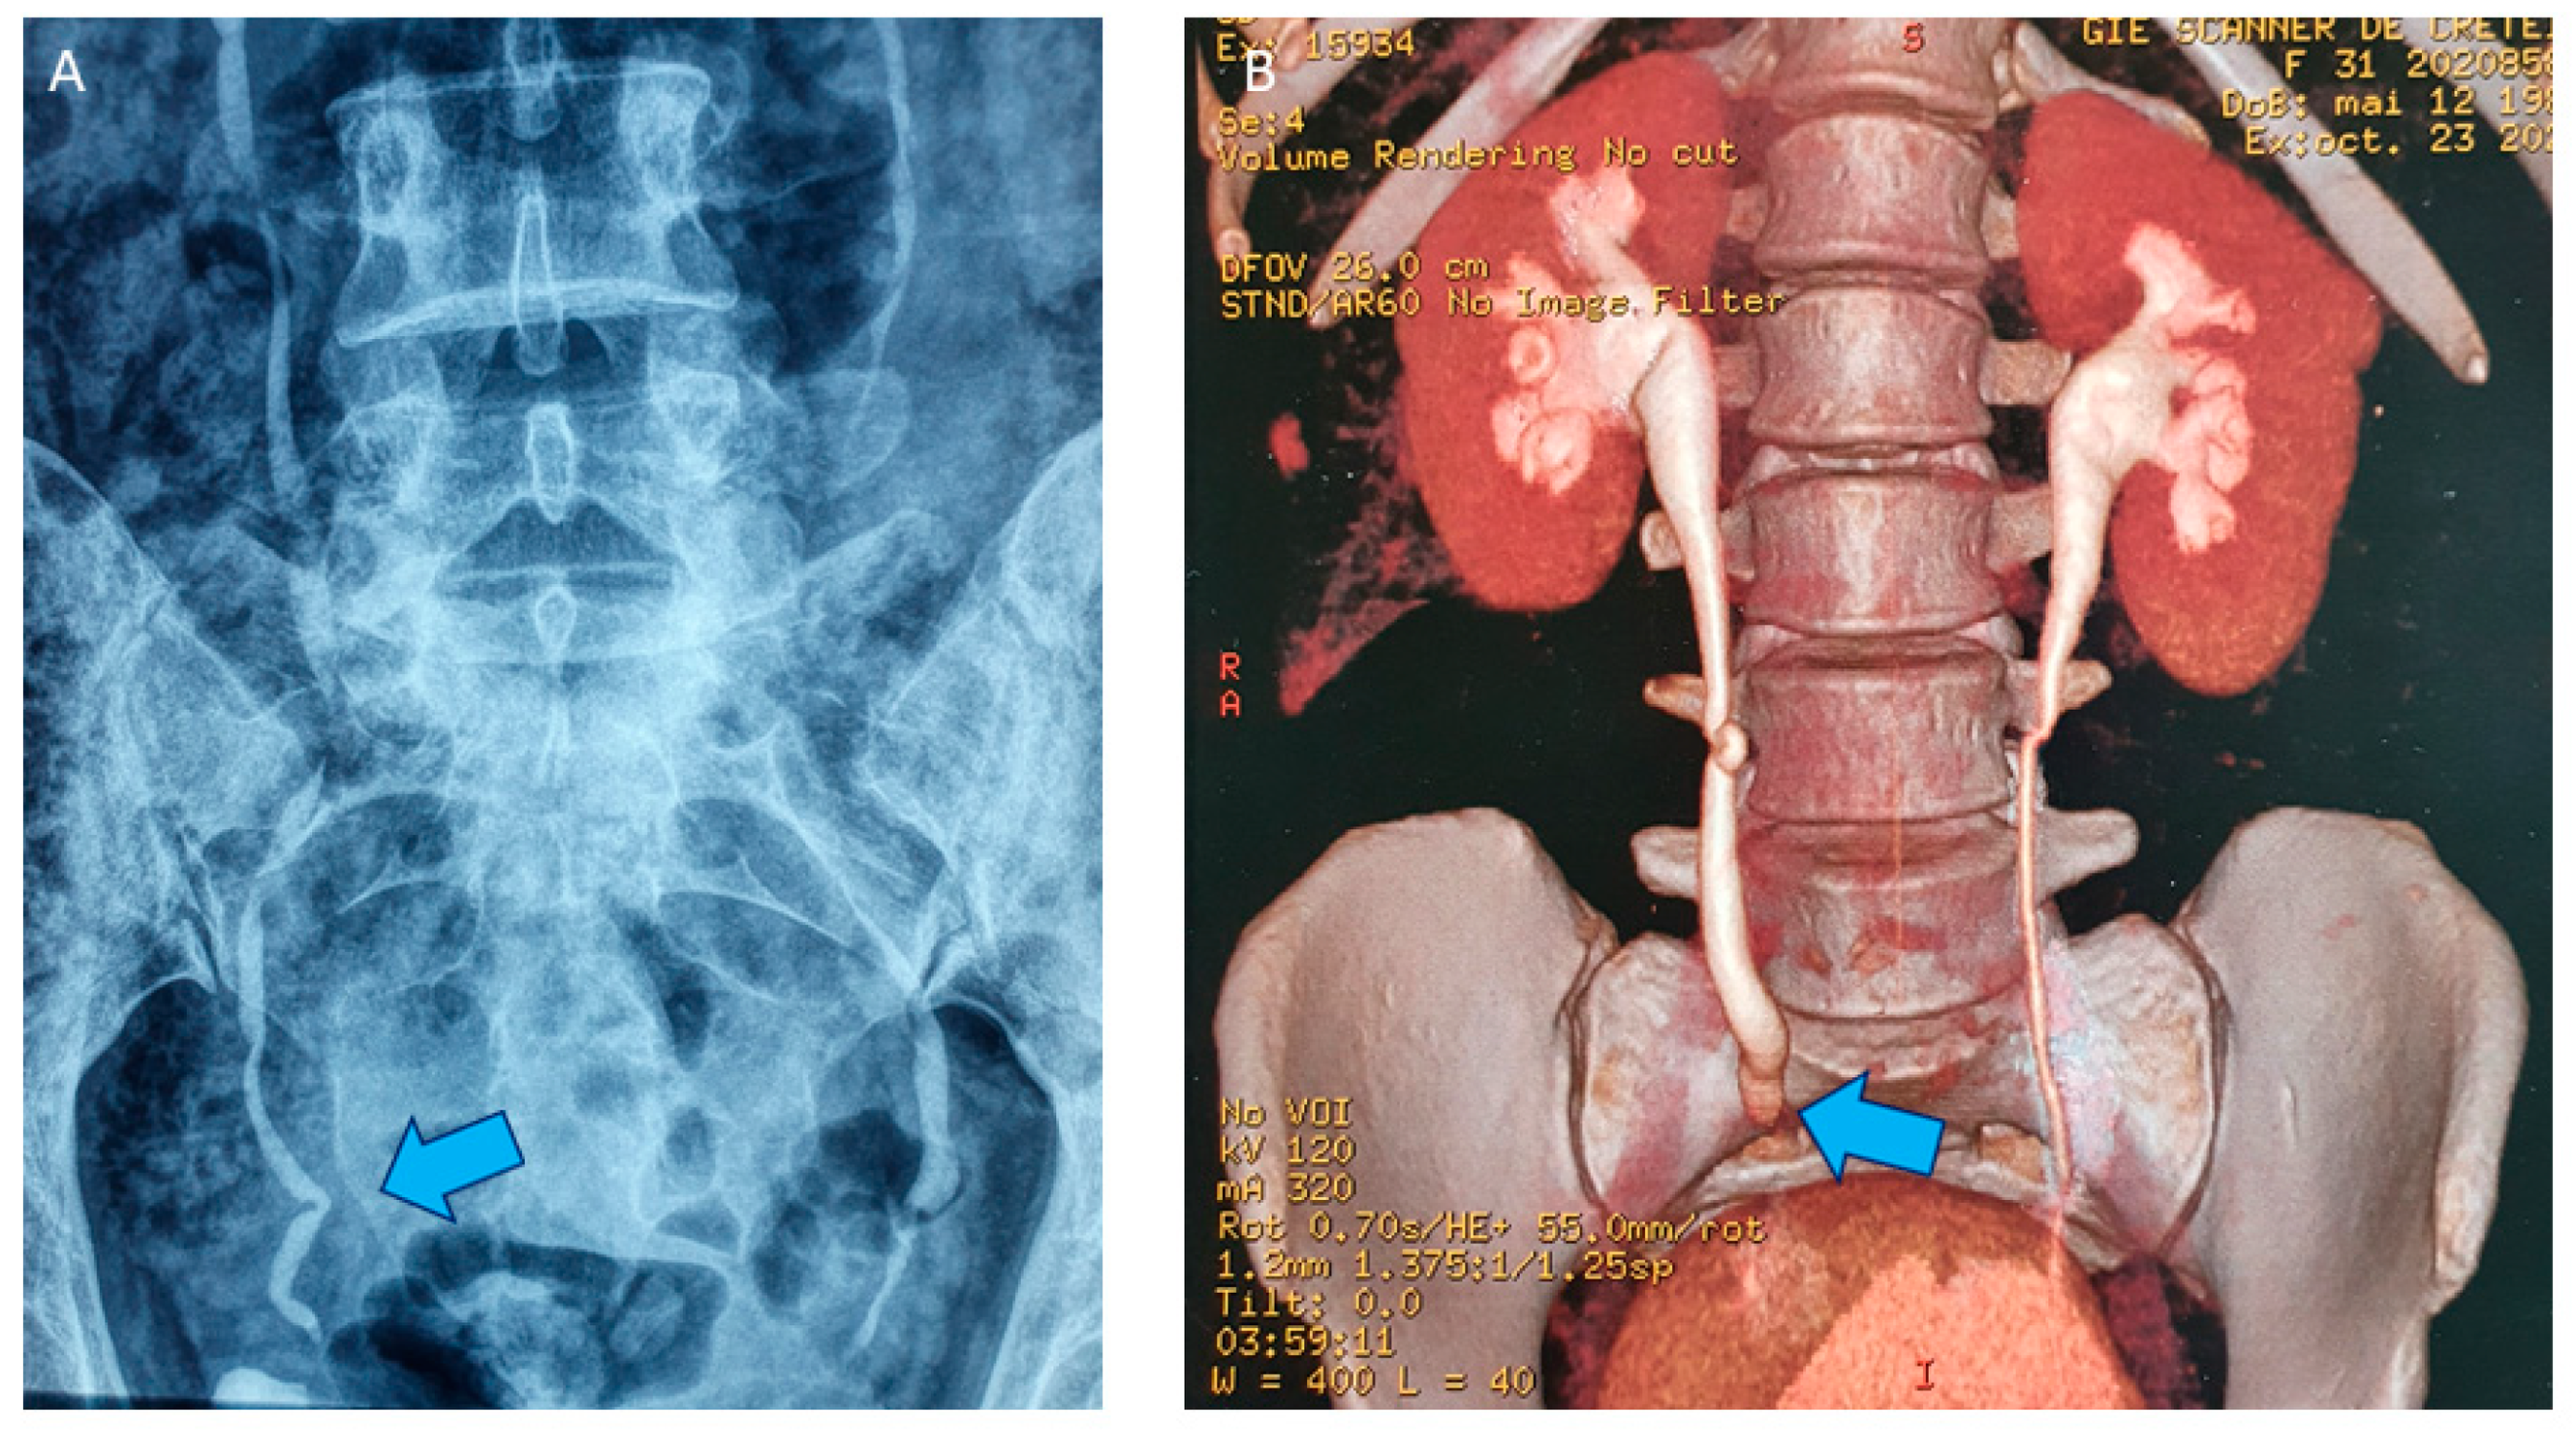

- Donnez, J.; Nisolle, M.; Squifflet, J. Ureteral endometriosis: A complication of rectovaginal endometriotic (adenomyotic) nodules. Fertil. Steril. 2002, 77, 32–37. [Google Scholar] [CrossRef]

- Jadoul, P.; Feyaerts, A.; Squifflet, J.; Donnez, J. Combined laparoscopic and vaginal approach for nephrectomy, ureterectomy, and removal of a large rectovaginal endometriotic nodule causing loss of renal function. J. Minim. Invasive Gynecol. 2007, 14, 256–259. [Google Scholar] [CrossRef]

- Knabben, L.; Imboden, S.; Fellmann, B.; Nirgianakis, K.; Kuhn, A.; Mueller, M.D. Urinary tract endometriosis in patients with deep infiltrating endometriosis: Prevalence, symptoms, management, and proposal for a new clinical classification. Fertil. Steril. 2015, 103, 147. [Google Scholar] [CrossRef]

- Maccagnano, C.; Pellucchi, F.; Rocchini, L.; Ghezzi, M.; Scattoni, V.; Montorsi, F.; Rigatti, P.; Colombo, R. Ureteral endometriosis: Proposal for a diagnostic and therapeutic algorithm with a review of the literature. Urol. Int. 2013, 91, 1–9. [Google Scholar] [CrossRef] [PubMed]